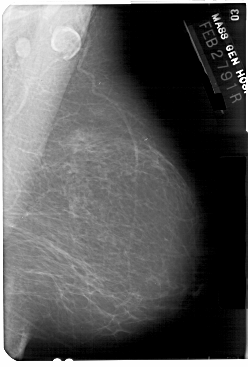

A_1375_1.LEFT_MLO

LEFT_MLO LINES 5491 PIXELS_PER_LINE 3601 BITS_PER_PIXEL 12 RESOLUTION 43.5 OVERLAY